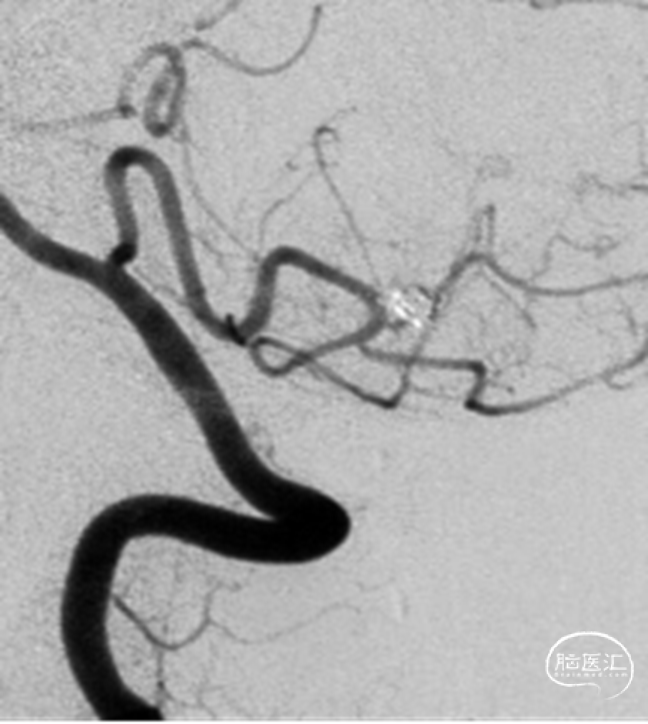

2、影像学随访:一年后的随访影像显示动脉瘤完全不显影。

一年后的随访影像